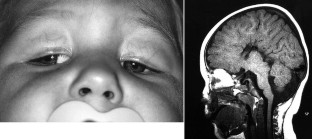

Clinical examination and forced duction testing confirmed that all four patients met criteria for CFEOM; all had congenital restrictive ophthalmoplegia primarily affecting extraocular muscles innervated by the oculomotor nerve. Two brothers had CFEOM and Marcus Gunn jaw winking. In each of the four cases, CFEOM occurred in association with one or several neuroradiological findings, including agenesis of the corpus callosum, colpocephaly, hypoplasia of the cerebellar vermis, expansion of the ventricular system, pachygyria, encephalocele and/or hydrancephaly.

Fig. 3.

Fig. 4.